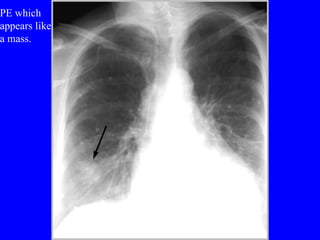

Diagnosis CXR Usually reveals a non specific abnormality.  14% normal Classic abnormalities include: Westermark’s Sign - focal oligemia Hampton’s Hump - wedge shaped density Enlarged Right Descending Pulmonary Artery (Palla’s sign)

PE which  appears like a mass.